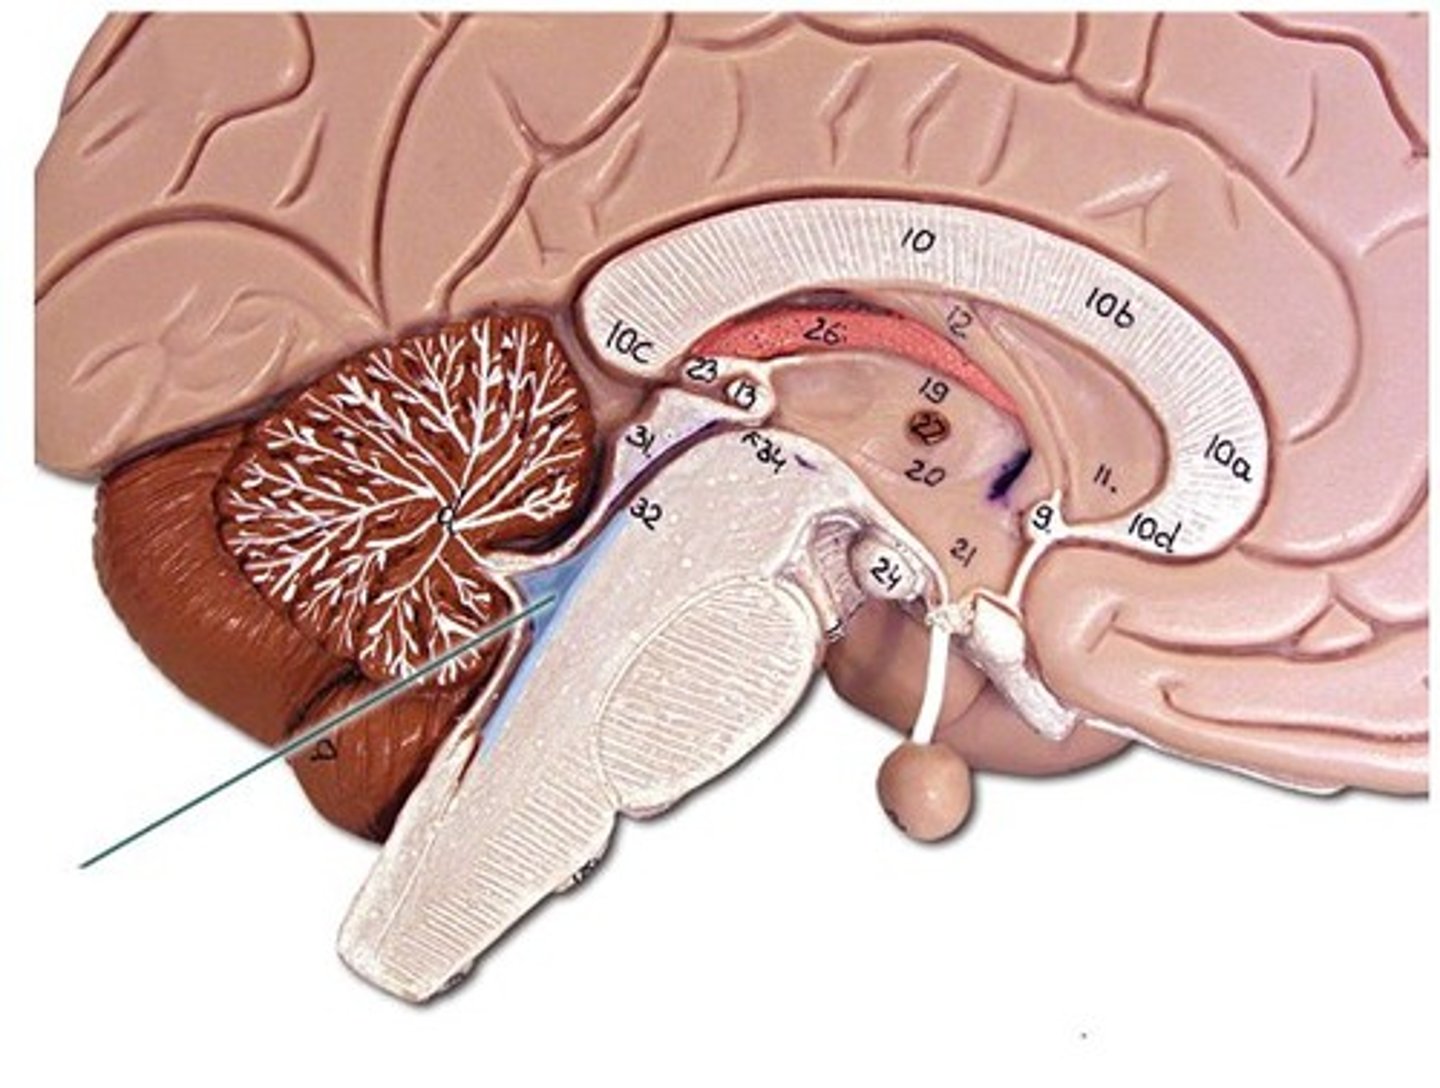

cerebellum

arbor vitae

white matter of the cerebellum

cerebellar hemisphere

vermis

Connects the two hemispheres of the cerebellum

cerebral aquaduct

fourth ventricle

medulla oblongata

midbrain

thalamus

hypothalamus

pituitary gland

pineal gland

pons